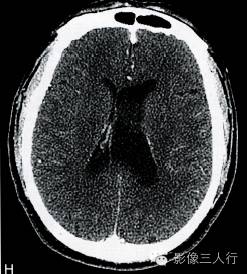

A.T2WI横断面;B.T1WI横断面;CFLAIR冠状面;D、E、F.增强横断面、矢状面、冠状面;G、H.CT平扫、增强;I.HE×100

肿瘤呈类圆形,边界清楚,位于左侧脑室前角及室间孔区,左侧脑室前角、三角部及左侧脑室后角扩张积水。MRI平扫T2WI(图A)肿瘤呈稍高信号,内见小范围高信号区;T1WI(图B)肿瘤呈等信号,内见低信号区;冠状面水抑制相(图C)肿瘤呈稍尚信号,内部原长T1长T2区信号呈低信号;增强扫描(图D~F)肿瘤强化不明显;CT平扫(图G)左侧脑室前角类圆形、边界清楚、较均匀等密度肿块,增强扫描(图H)强化不明显。